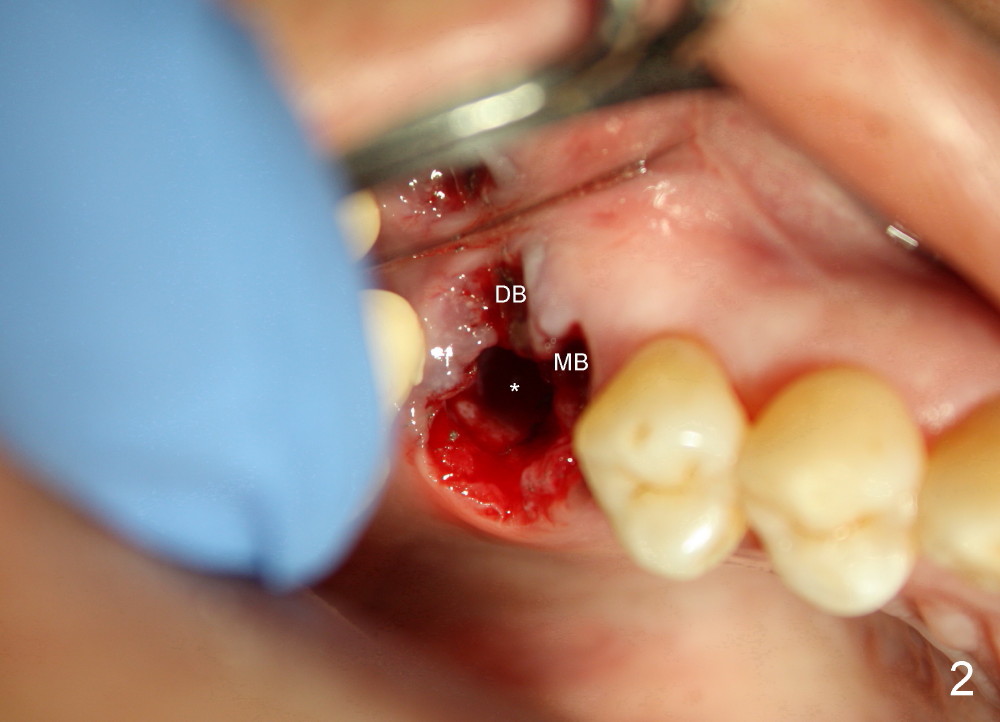

Lack of bony support and soft tissue coverage appear to be an obstacle to immediate implant. Two cases are presented. The first one is my first attempted immediate implant patient (Fig.1-3), a 54-year-old lady. She is extremely apprehensive. The upper right first molar has severe perio-endo disease. There is no bone around the buccal roots (MB, DB in Fig.1). The tooth is non salvageable and is treated the best with an immediate implant. When the tooth is extracted, the large buccal gingival defects (Fig.2 MB, DB) and sinus perforation (Fig.3) through the palatal socket (Fig.2 *) are apparent contraindications to immediate implant. Amazingly, the gingiva heals rapidly post extraction. An implant is placed 1 month later.